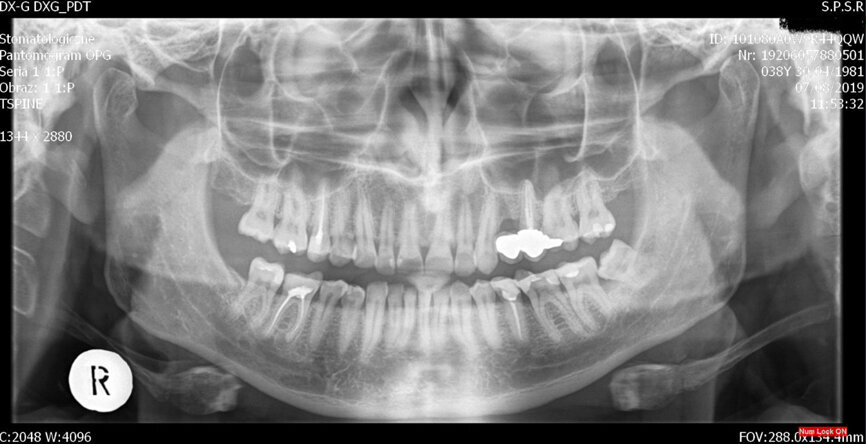

On examination, it was noticed that tooth #26 was tender to cold and sweet. A panoramic radiograph revealed the presence of dental caries penetrating to the pulp chamber (Fig. 1).

I decided on single-visit endodontic treatment. The treatment began with administration of local anaesthetic and dental dam isolation. Crown access was performed with a diamond bur and ultrasonic tip (CAVI 2-D, VDW), which was also used to perform the removal of the coronal portion of the pulp and canal localisation. On access, four canals were identified by inspection with an endodontic probe. The working length of the palatal canal was 21.5 mm (C-PILOT, ISO size 10, VDW), of the mesiobuccal and distobuccal canal was 21.0 mm (C-PILOT, ISO size 10), and of the second mesiobuccal canal was 20.0 mm (C-PILOT, ISO size 8). An electronic apex locator was used for working length confirmation. As can be seen in the panoramic radiograph and dental radiograph (Fig. 2), the canals were quite narrow and curved, so I decided to use rotary files (VDW.ROTATE, VDW).